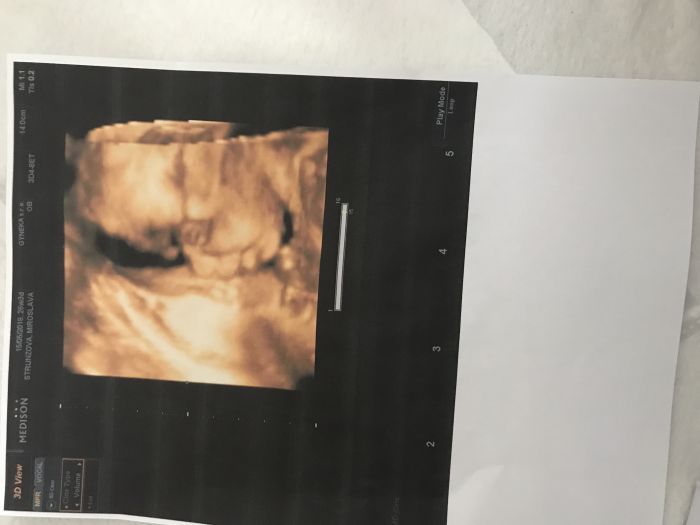

Byla jsem dnes na kontrole , kvůli častému tvrdnuti břicha , dostala magnesko ,jsem 26+3 a miminko už se nám krasne kulatí ❤️

Mirčo krásná fotka, paráda!